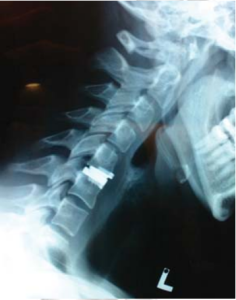

Lateral cervical spine flexional and extension x-rays show good movement of the cervical spine, this is important if we are planning to insert an artificial disc.